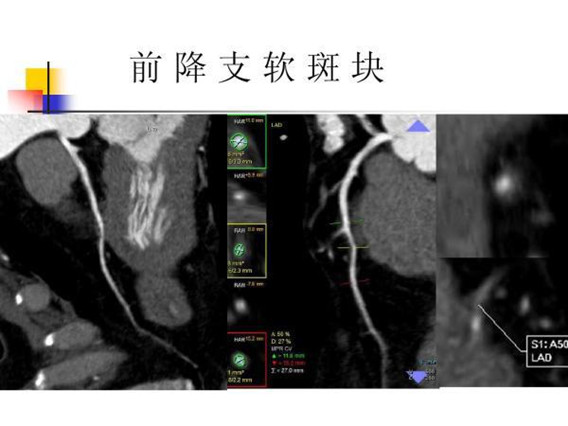

CTA成像检查在临床上可用于:(1)心脏表面成像:观察心脏表面形态、瓣膜结构、心肌厚度、心脏长短轴分析;(2)冠状动脉树成像:能显示冠状动脉的3-4级分支,可诊断冠状动脉狭窄、动脉粥样硬化、评估冠脉内支架和搭桥术后疗效;(3)分析和评估心脏功能,如心机灌注情况、左心室射血分数、室壁运动等(4)冠状动脉钙化积分:可对冠状动脉钙化进行精确定量,评估冠状动脉钙化程度和范围,是对冠心病进行早期普查的理想的无创的检查方法。CTA与传统动脉插管血管造影(DSA)相比,具有安全性高,检查过程便捷,费用低廉等优势。